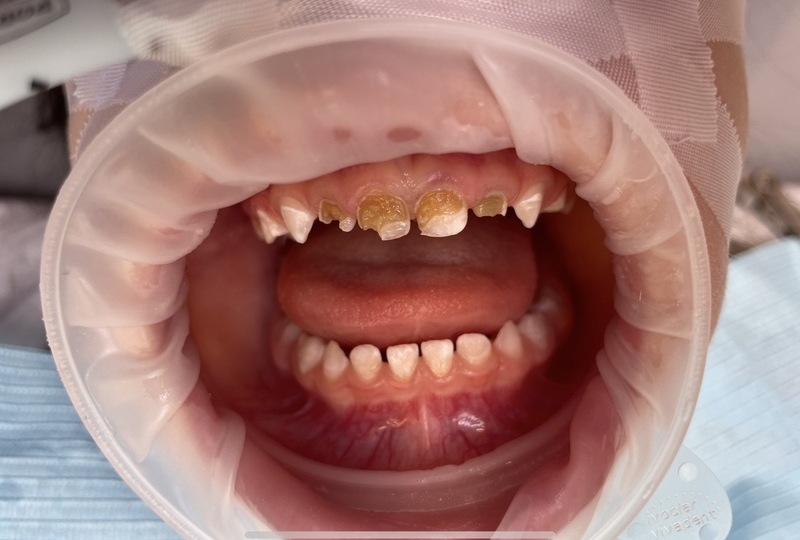

Situace se v některých oblastech zlepšuje, ale stále existuje velká skupina lidí, kteří péči o zuby zanedbávají. „Kazivost zubů je v Česku stále poměrně vysoká a řešení následků komplikované a drahé,“ dodává. Trend „rozevírajících se nůžek“ mezi těmi, kdo prevenci dodržují, a těmi, kdo zanedbávají, je patrný.

Jednoduché pravidlo „Čistý zub se nezkazí“ shrnuje princip prevence: kaz vzniká, když na zubech zůstává bakteriální plak. Pravidelné a důkladné čištění chrání zuby. Důležitá je i role rodičů: děti si zuby správně vyčistí samy až kolem deseti let, do té doby je třeba je učit a kontrolovat.

Životní styl, například časté sladké nápoje a průběžné „uzobávání“, zvyšuje riziko vzniku kazu. Moderní technologie jako elektrické kartáčky mohou pomoci, ale klíčová je pravidelnost a důslednost.